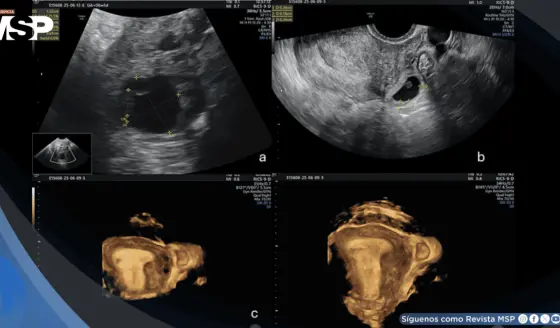

Embarazo intersticial tras transferencia de embriones congelados en paciente con salpingectomía bilateral